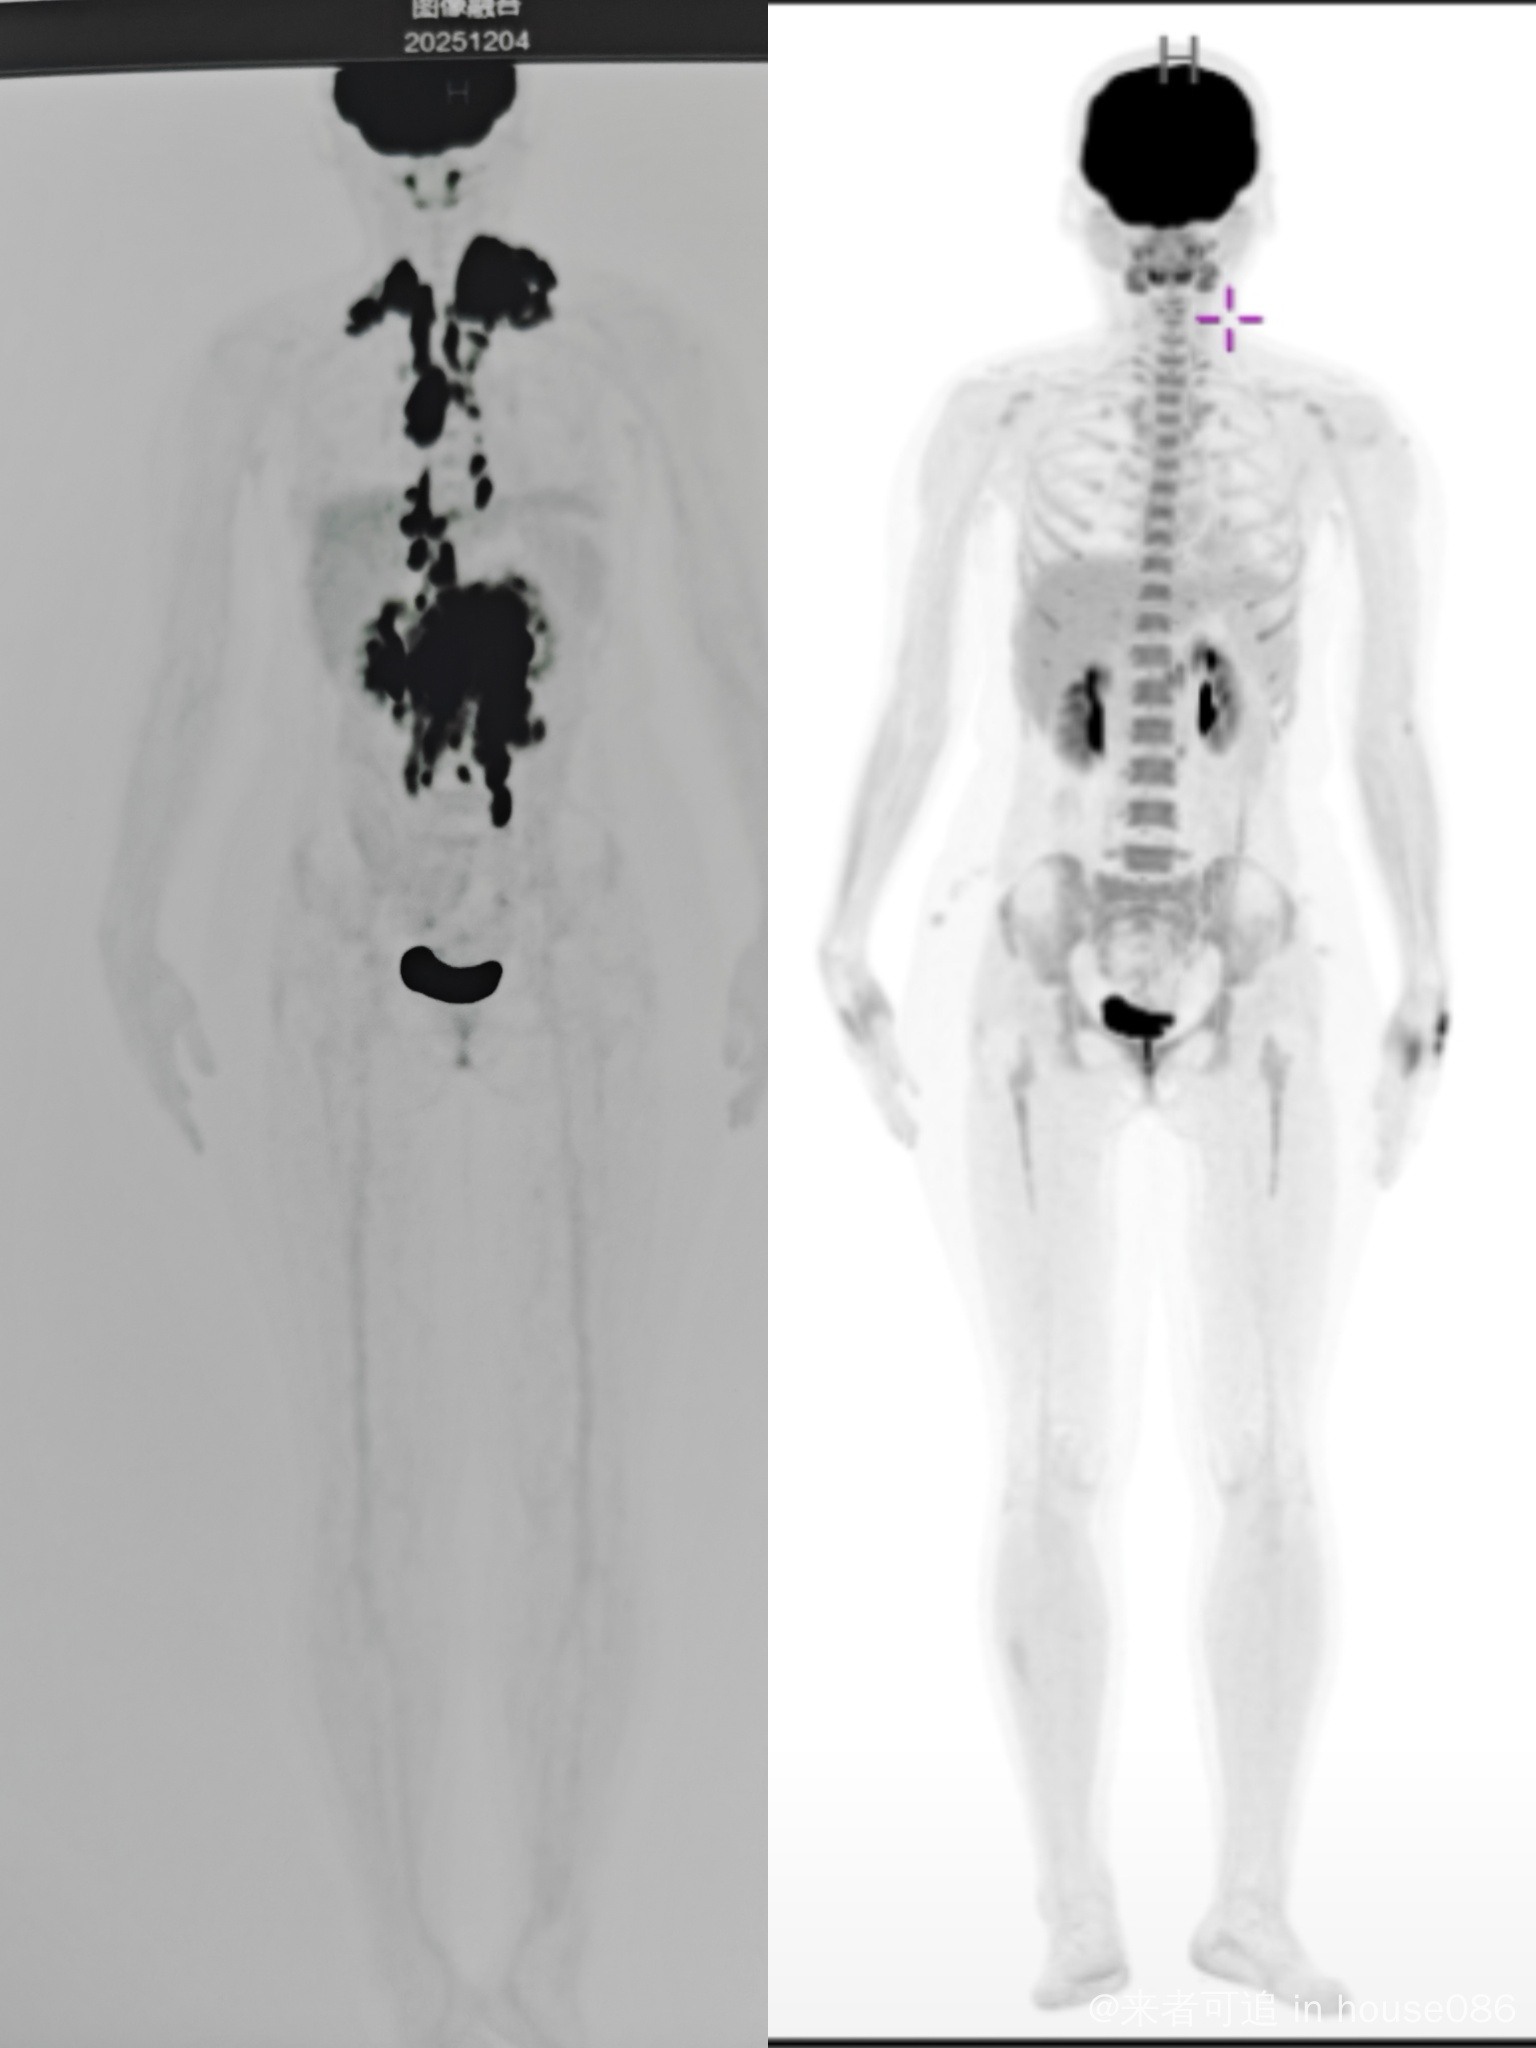

滤泡3b部分转弥漫大b,用的pola-r-chp方案,五疗前做的pet,结果是pr,还剩下腹部suv4.4的病灶,还有2次联合用药和2次单抗用药,结疗前cr应该问题不大吧?@橙色雨丝